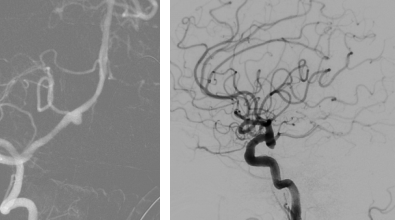

脑血管造影(DSA):这是确诊并锁定动脉瘤的“金标准”。医生通过它能看到脑血管的清晰三维结构,明确“炸弹”的位置和形态,为手术铺路。

血管内介入治疗(栓塞术):

从大腿血管“打隧道”进去,用弹簧圈填塞动脉瘤,或用支架辅助封堵。这是目前的主流微创治疗方法。

目标只有一个:尽快将“定时炸弹”(动脉瘤)处理掉,防止再次破裂(再出血死亡率极高)。